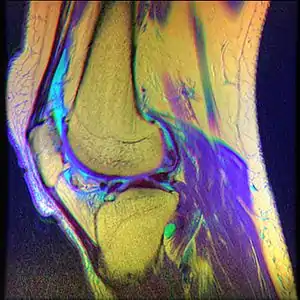

| Diagnostic method | MRI |

- Magnetic Resonance Imaging (MRI) – to observe cartilage condition and assess deterioration